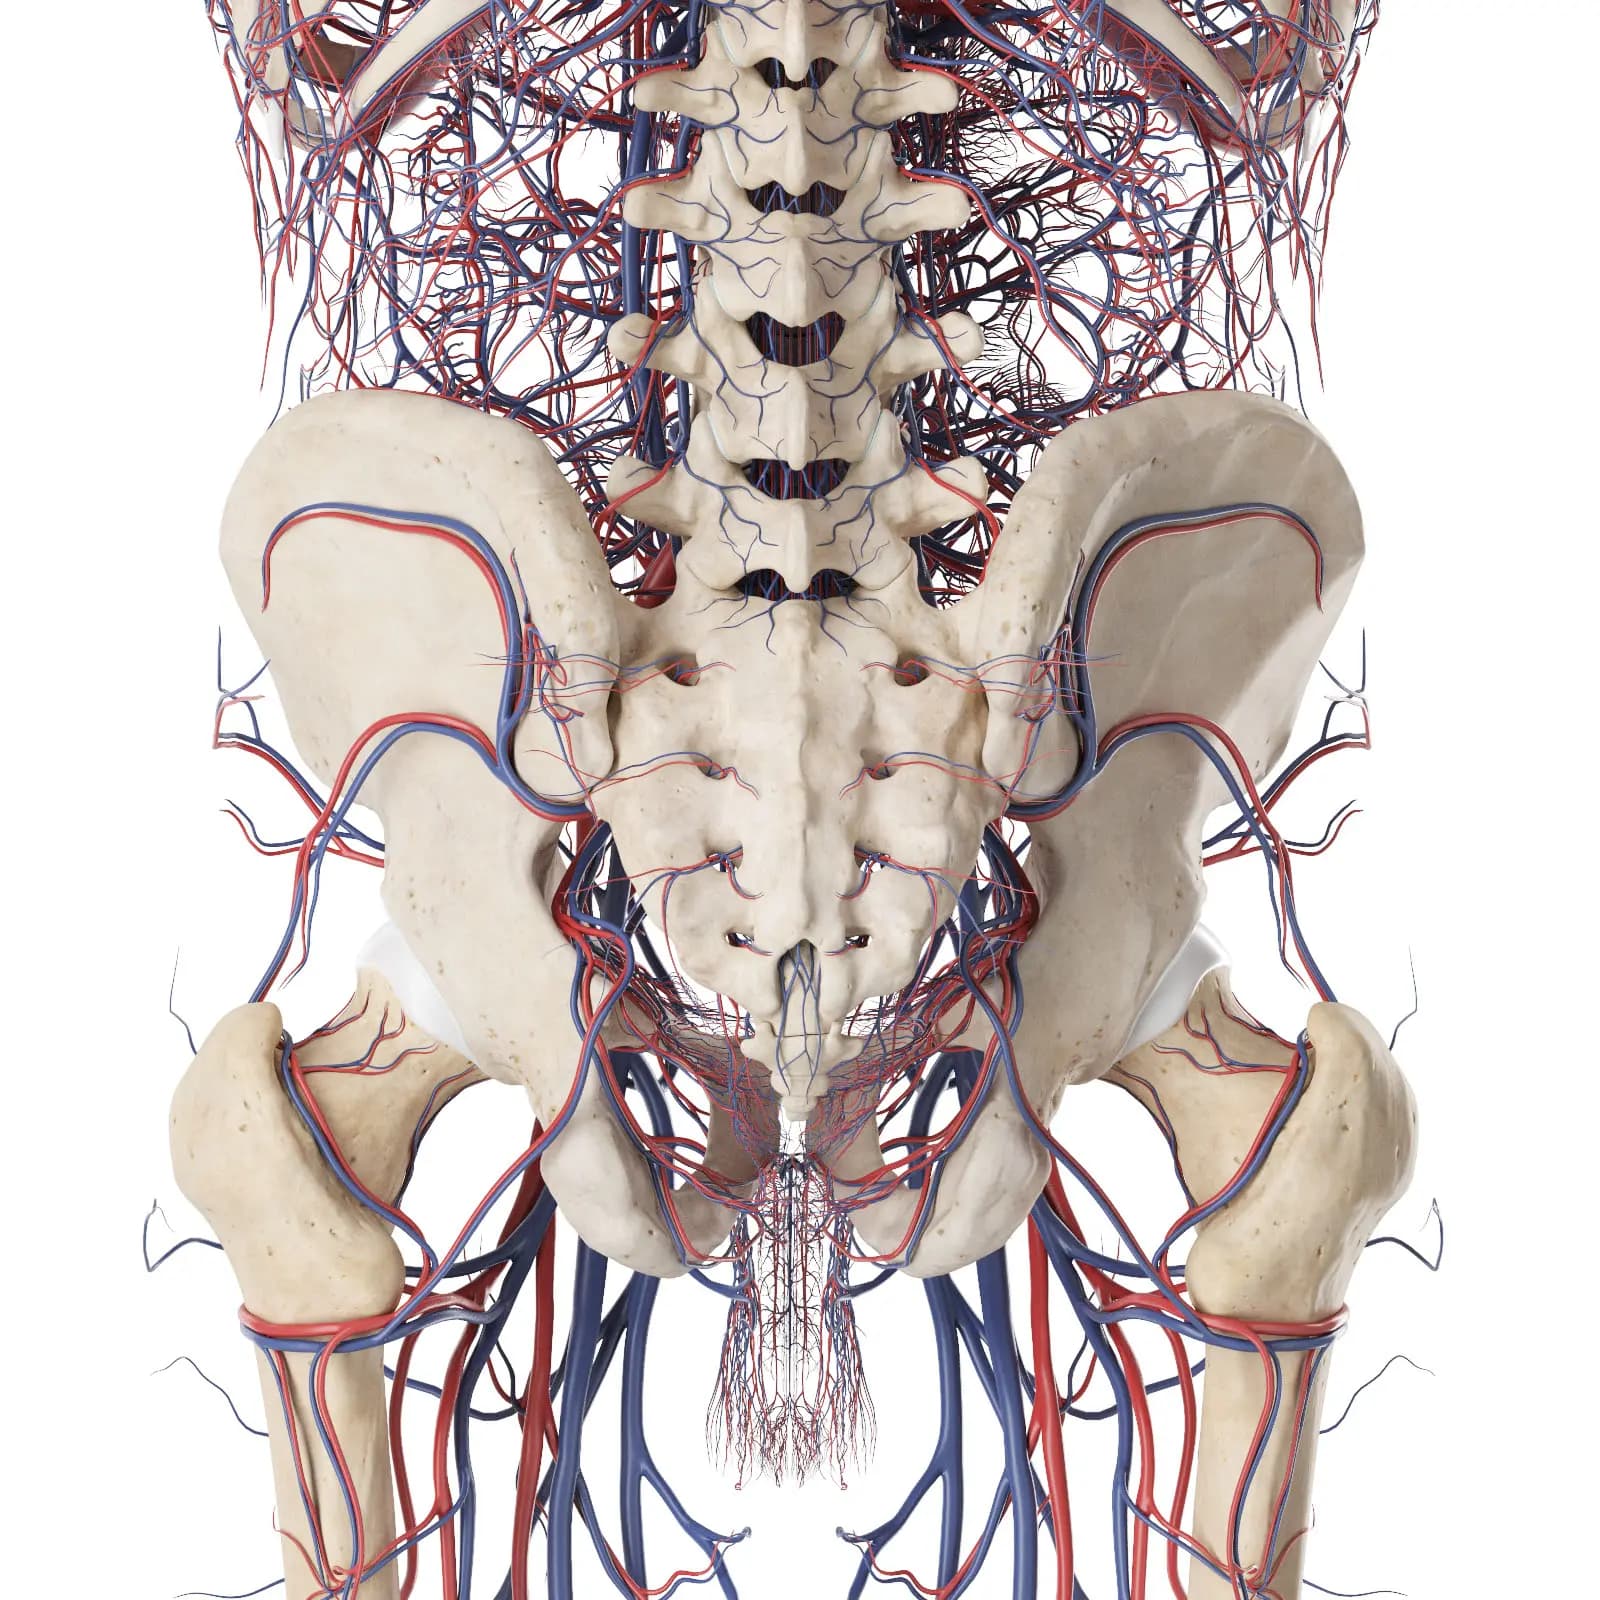

3d Rendered Medical Illustration Of The Vascular System Of The Back